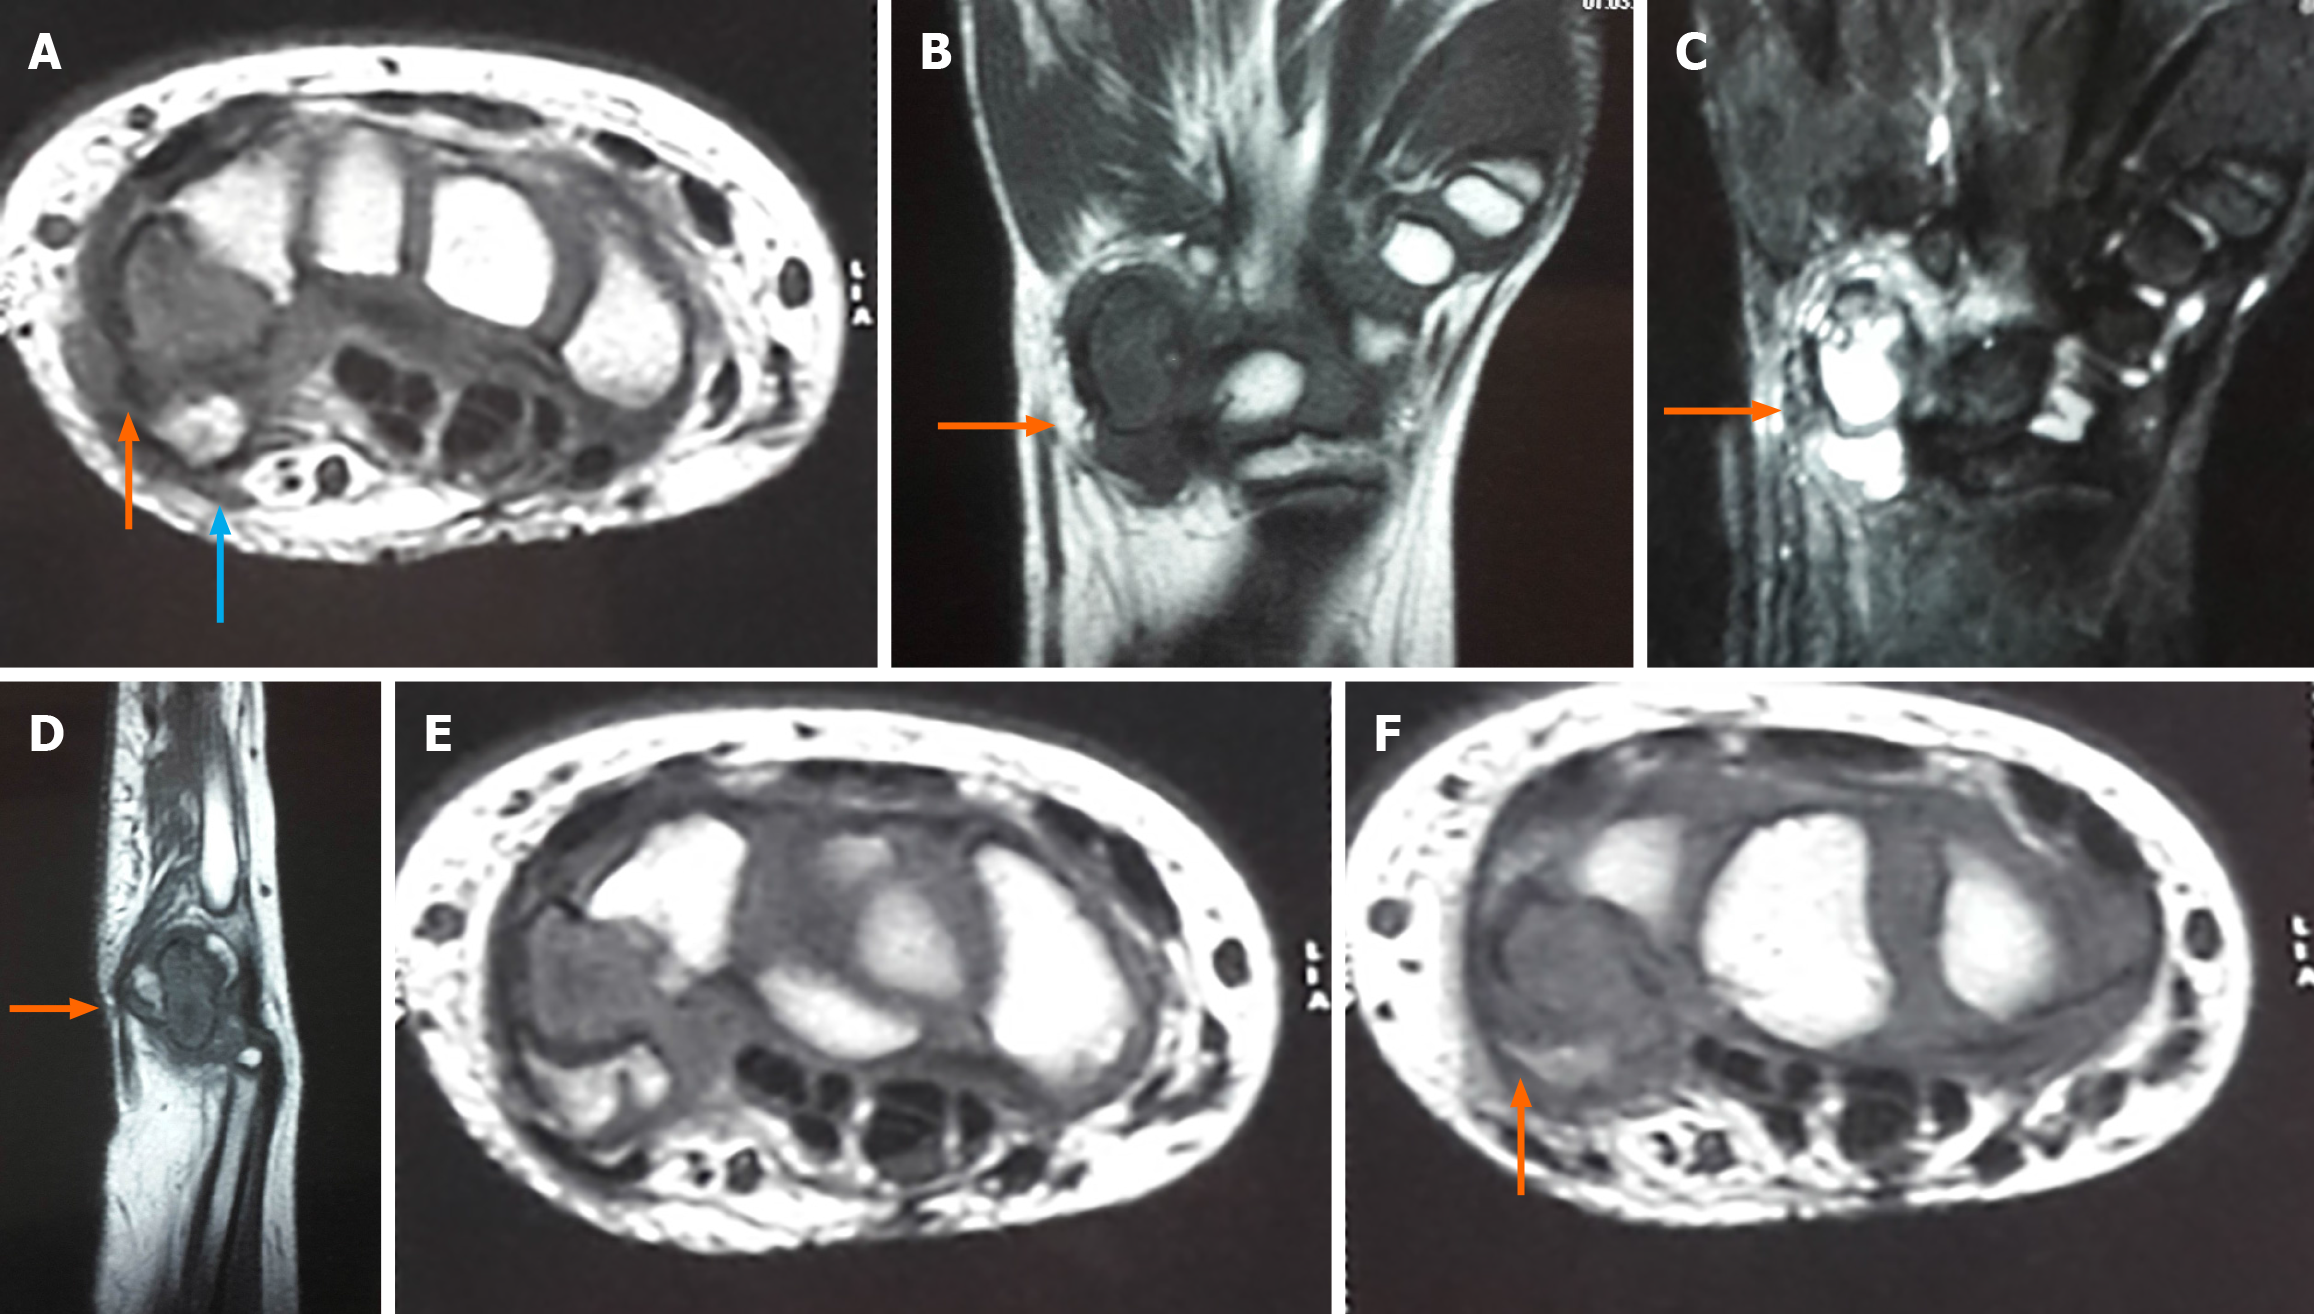

Figure 3 Magnetic resonance imaging.

A-F: T1 coronal with hyointense lesion marked (B); T2 coronal with oedema of the pisiform and triquetrum without adjacent soft tissue infiltration marked (C); T1 sagittal with hypointense lesion marked (cartilage caps are hypointense in T1) (D); T1 axial with hypointense lesion marked and ventral isointense lesion suggestive of pisiform (orange arrow) with dorsal lesion (blue arrow) (A, E and F).